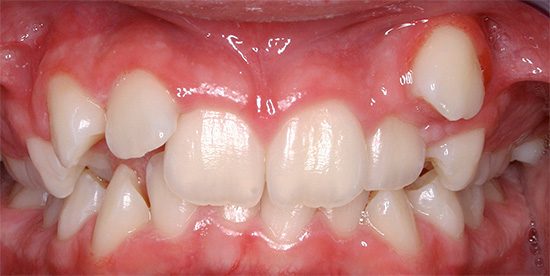

La fotografia sotto mostra un esempio di morso incrociato in un adulto:

Reclami frequenti da pazienti e genitori:

- la presenza di un difetto estetico con una notevole discrepanza tra dimensione e posizione delle mascelle;

- difficoltà a mangiare;

- violazione della pronuncia del suono;

- malattia gengivale dovuta a possibili lesioni durante la masticazione e la parola;

- problemi al tratto gastrointestinale.